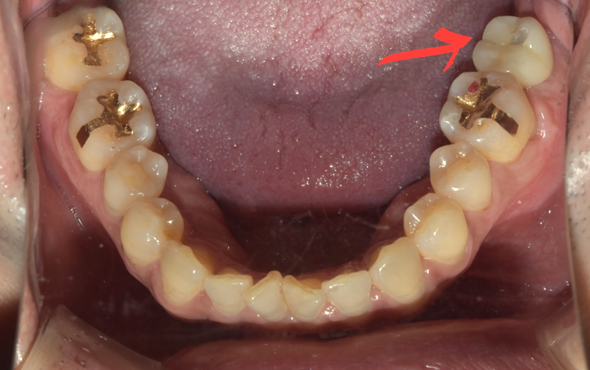

앞서 말씀드린 SCRP 방식으로 치료를 마친 모습입니다.

(후) 2022-01-18

추가로 설명해 드린다면, 이 환자분은 아스피린을 복용 중이셨는데요.

아스피린은 피를 맑게 하는 항혈전제이기 때문에 수술 후 지혈을 어렵게 합니다.

그러므로 안정적인 임플란트 시술을 위해선 일주일간 조절이 꼭 필요합니다.

그렇다고 환자분이 복용 중인 약을 임의로 중단하는 것은 위험할 수 있습니다.

따라서 수술 부위와 깊이, 예상 출혈량에 대해 담당 치과 선생님과 충분히 상의한 후 항혈전제를 처방한 주치의와 최종 상의해서 약물 중단 여부를 결정해야 합니다.

이는 아스피린뿐만 아니라, 다른 약물들도 치료와 예후에 영향을 줄 수 있으므로 담당 의사에게 복용 중인 약물, 기저질환 등을 정확하게 알리셔야 합니다.